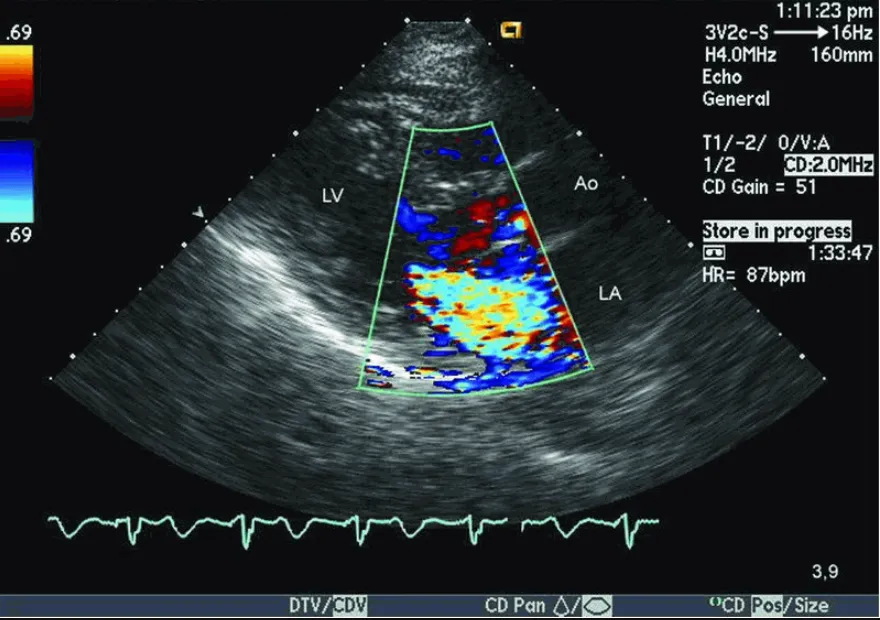

Siêu âm tim Doppler cho thấy hở van hai lá.

• Bệnh van tim: Siêu âm tim có thể đánh giá chức năng của các van tim (van hai lá, van ba lá, van động mạch chủ, van động mạch phổi) để phát hiện tình trạng hẹp hoặc hở van.